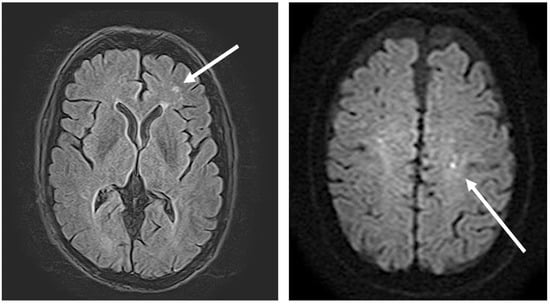

3.3. Central Nervous System Manifestations of Coccidioidomycosis and in This Patient